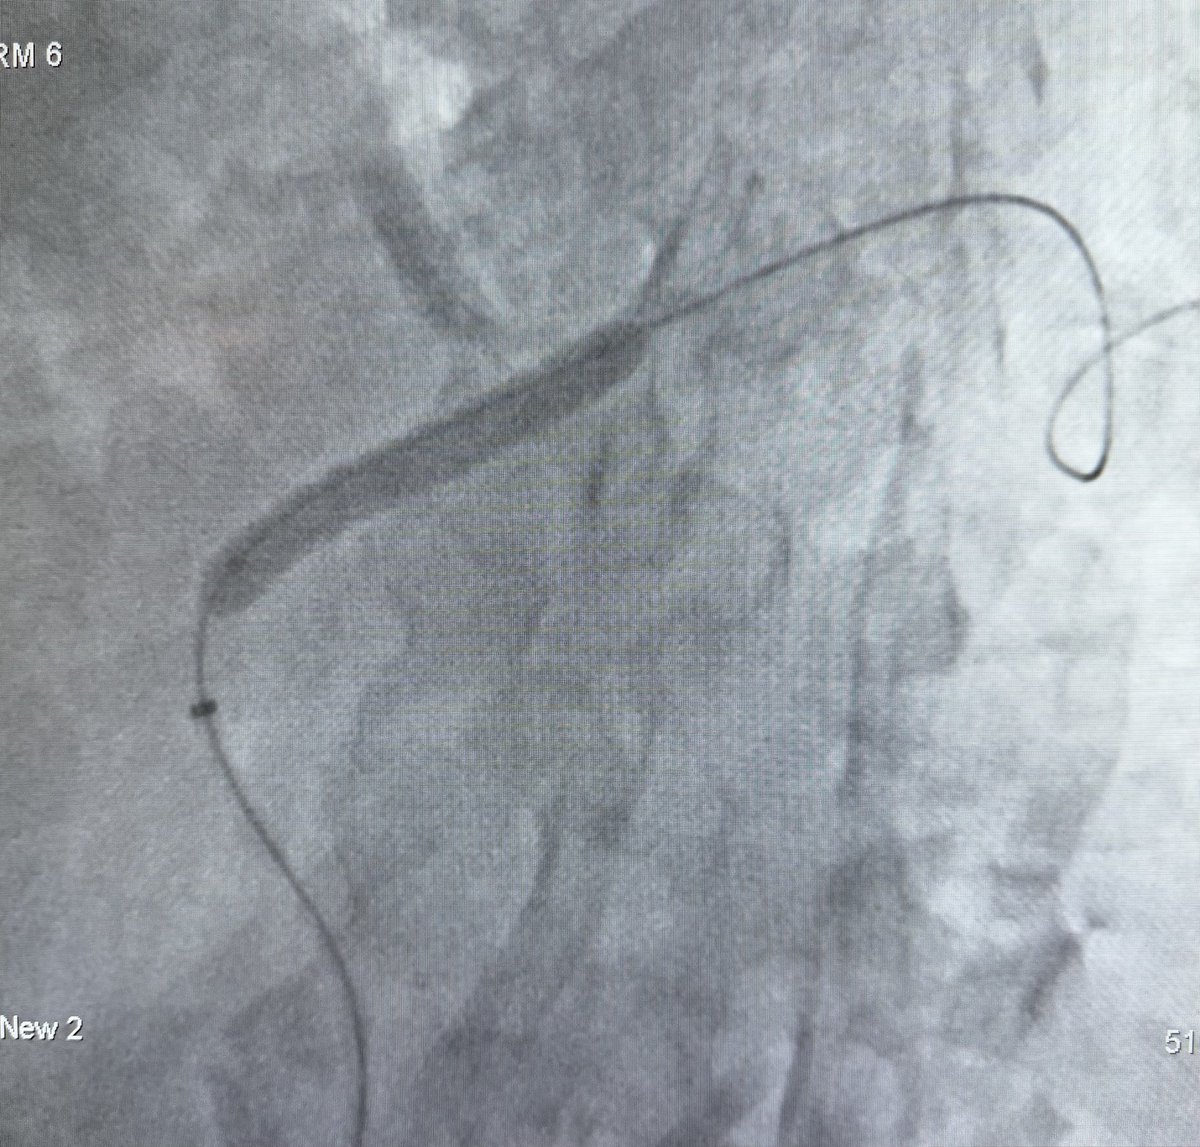

80 hrs of call #rupture #aorta #EVAR x2 #Endoanchors @MDT_Cardiac #DVT @Pen #GSW fem artery